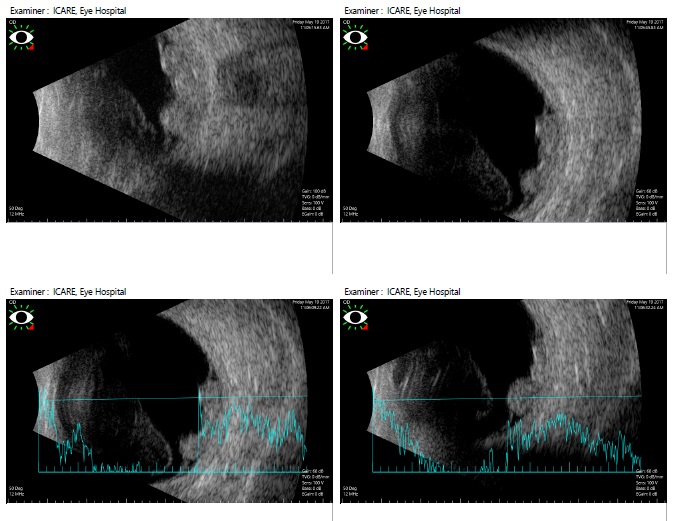

Ultrasonographic features of choroidal detachment (CD)

A CD is denoted by a round mound which is limited by the strong uveoscleral attachments (scleral spur, vortex veins, and optic nerve). It has limited mobility and an A scan passing perpendicularly through a CD shows 'M' (double peak) shape. The shape is typically of a smooth dome, usually not attached to the optic disc. The fluid in the suprachoroidal space may be anechoic (serous CD) or have mild to moderate amplitude point echoes (hemorrhagic CD). When CDs touch each other they are called kissing choroidals, and such cases may be more prone to permanent adhesion and may guide the timing of surgery in suprachoroidal hemorrhage. USG also notes the clot lysis in suprachoroidal hemorrhages and guides timing of surgery, and the location of the suprachoroidal hemorrhage guides the area of drainage.